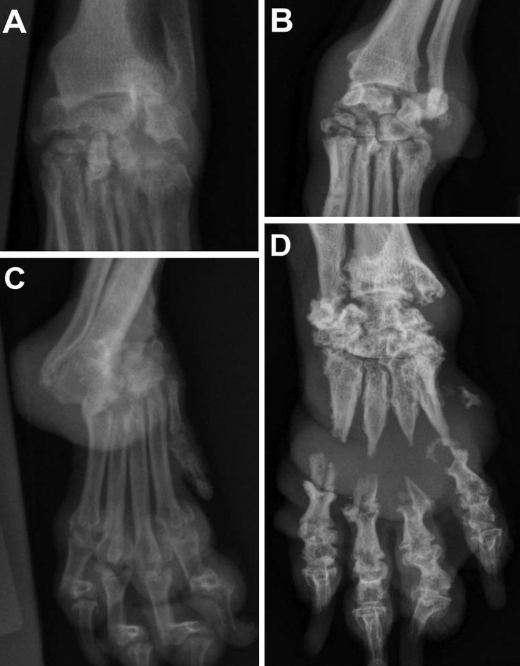

물론 이미 방치되어 골 융해수준이 심한 경우 치료를 하더라도 뼈가 다시 자라는것은 아니니 조기 진단과 조기 치료가 필수적이다.